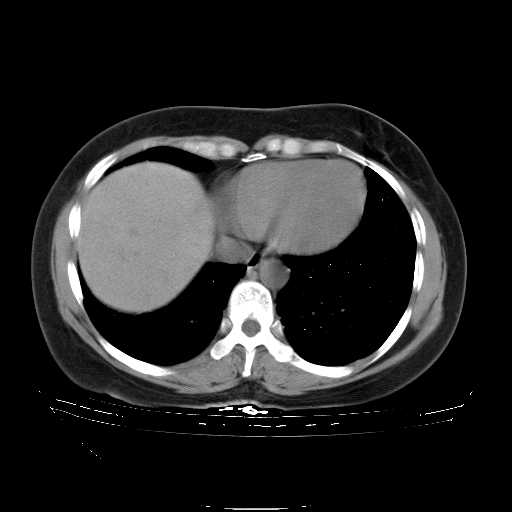

f50,肺ca治疗后,做过穿刺,确诊是肺ca,大家看看这是去年12月做的